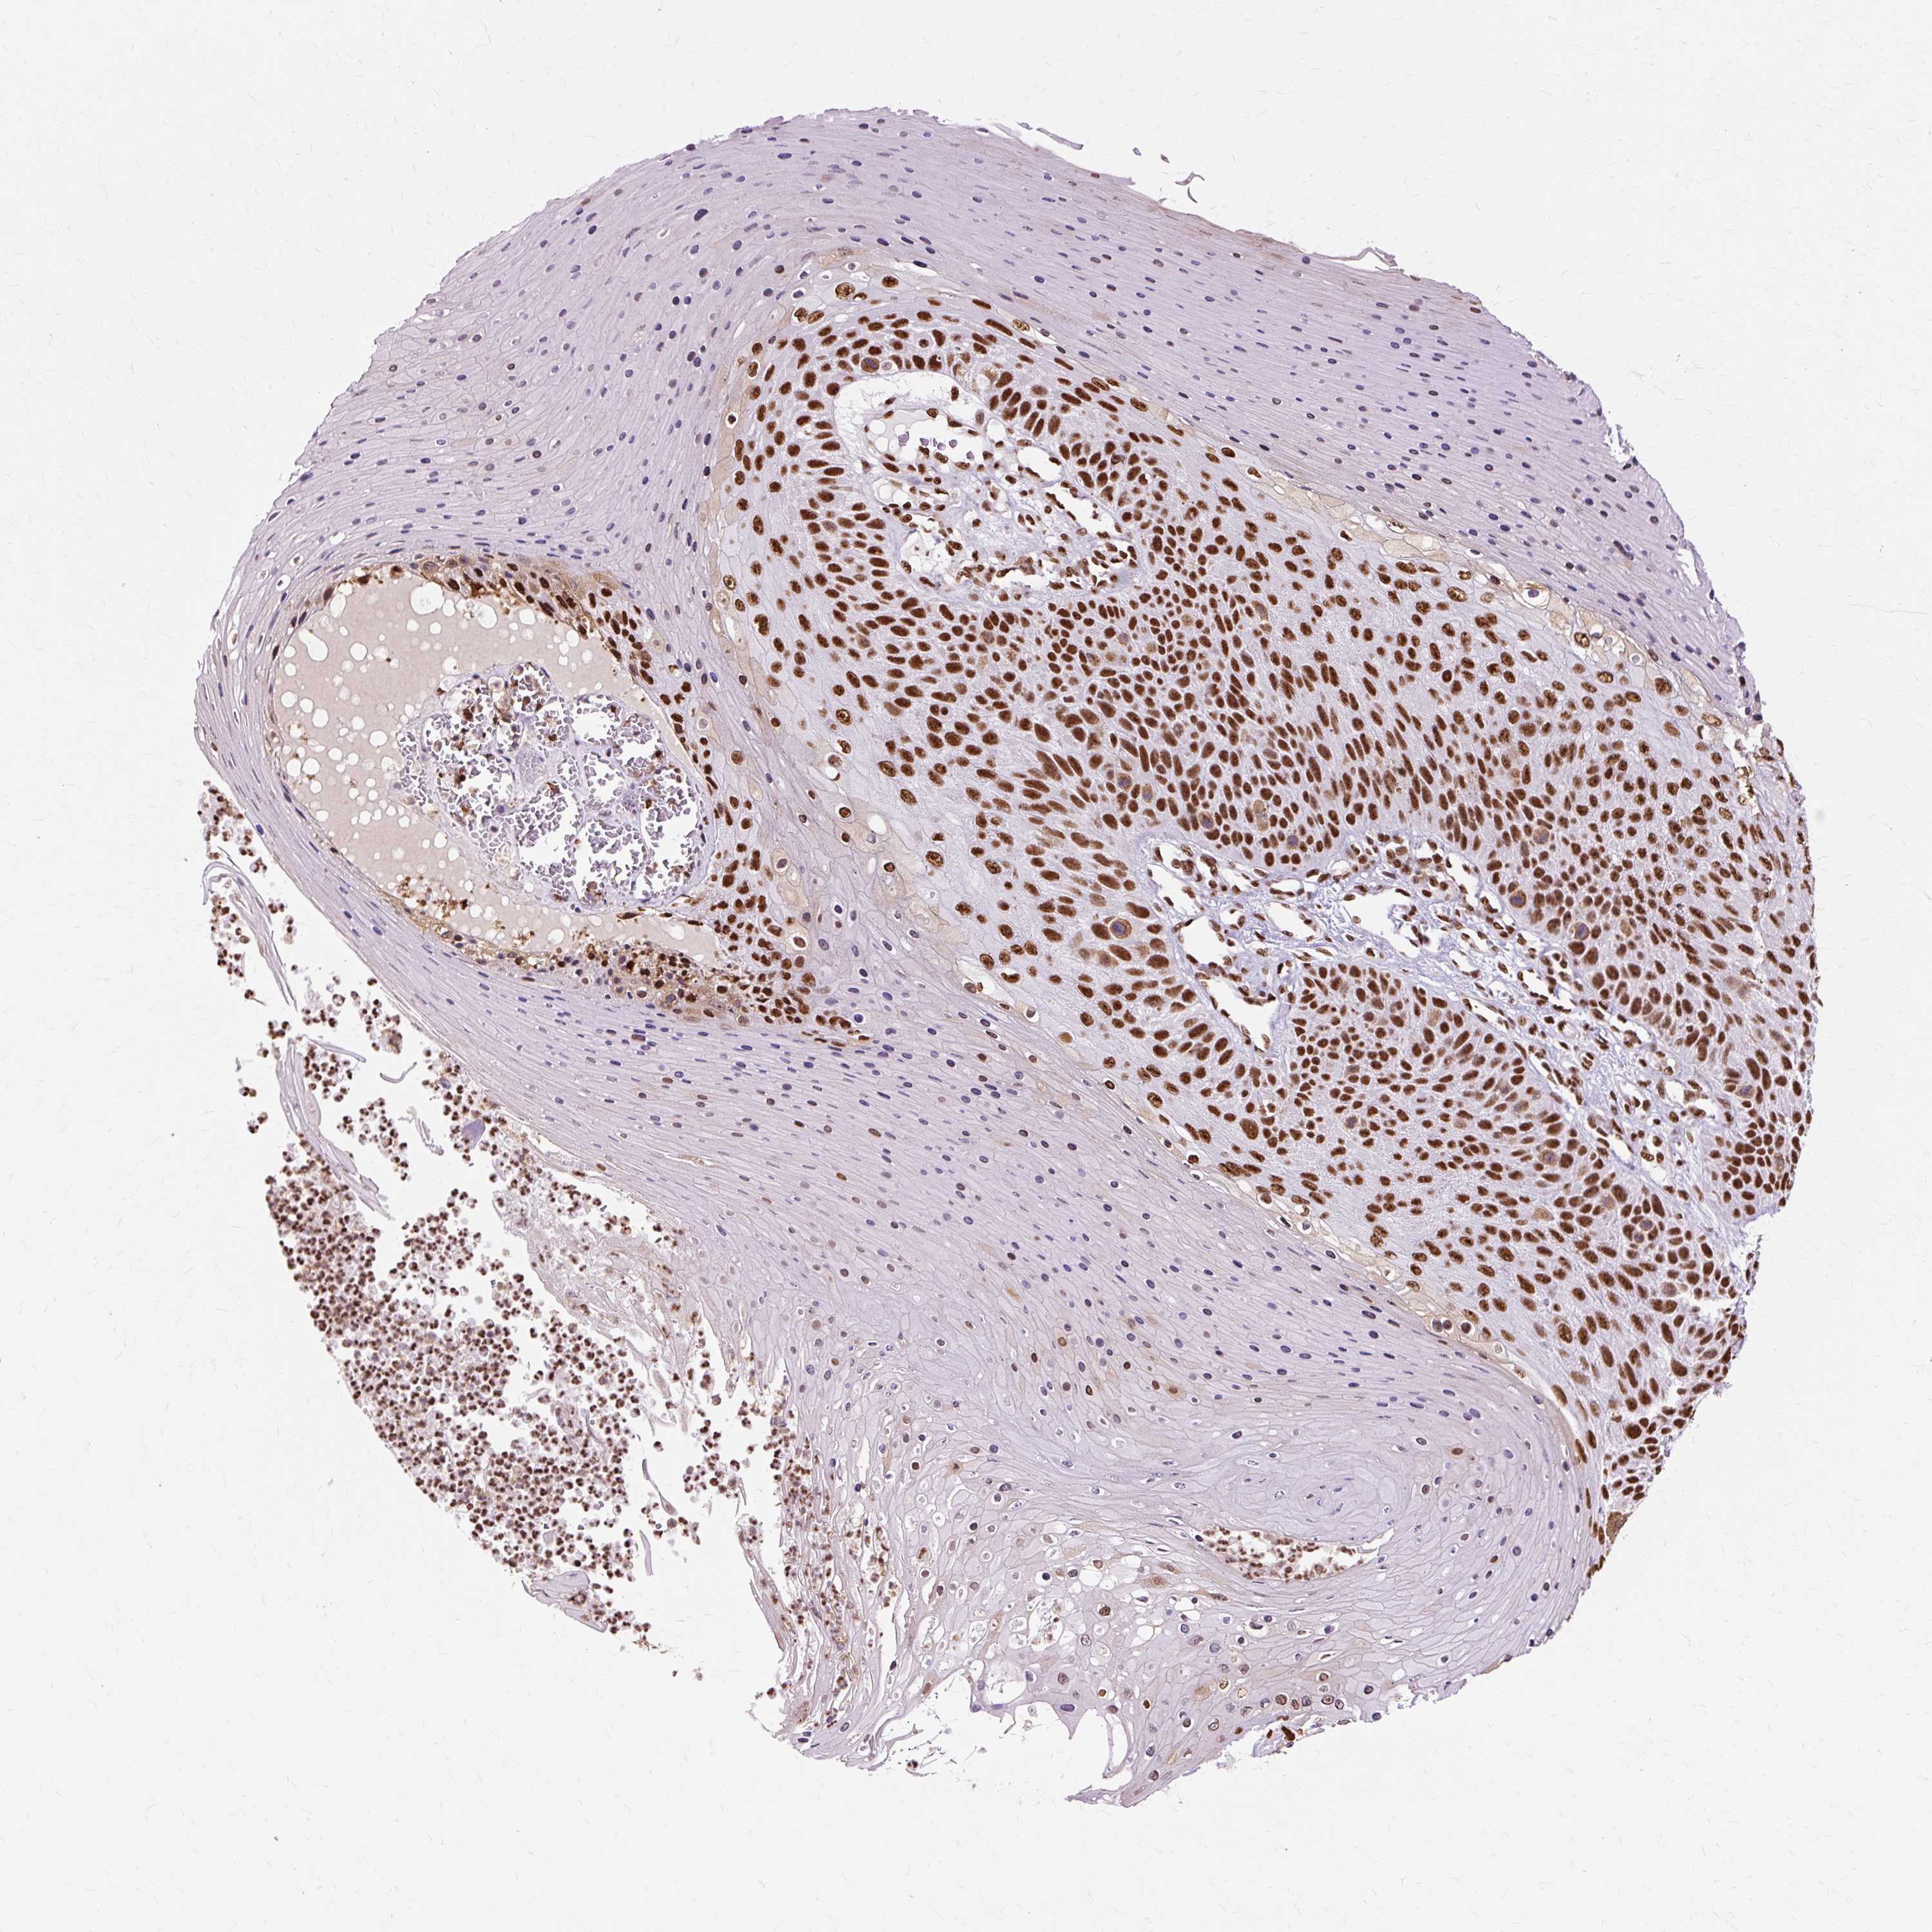

SKIN CANCER - Protein expressioni

A mouse-over function shows sample information and annotation data. Click on an image to view it in a full screen mode. Samples can be filtered based on level of antibody staining by selecting one or several of the following categories: high, medium, low and not detected. The assay and annotation is described here.

Antibody staining in the annotated cell types in the current human tissue is reported as not detected, low, medium, or high, based on conventional immunohistochemistry profiling in selected tissues. This score is based on the combination of the staining intensity and fraction of stained cells.

Each image is clickable and will lead to virtual microscopy that enables deeper exploration of all samples and also displays staining intensity scores, fraction scores and subcellular localization as well as patient and tissue information for each sample.

Antibody HPA047549

Staining

High

Intensity

Strong

Quantity

>75%

Location

Nuclear

Squamous cell carcinoma, NOS

Squamous cell carcinoma, metastatic, NOS

Basal cell carcinoma